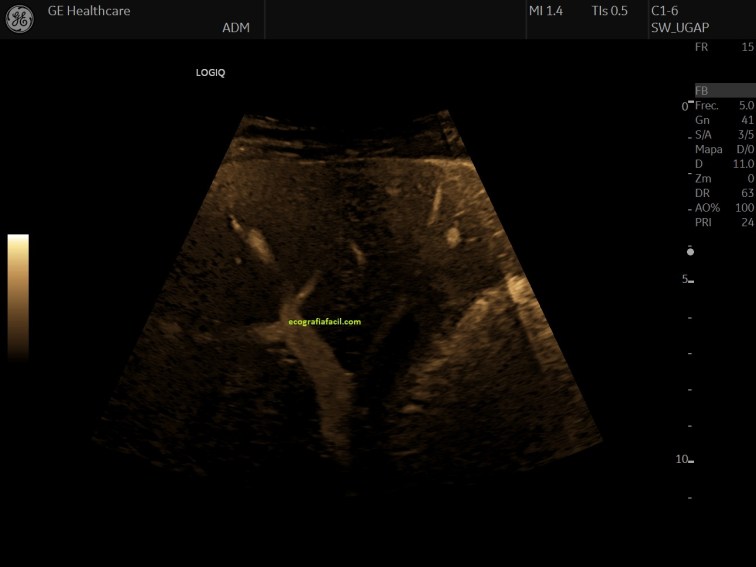

Os voy a dejar una serie de imágenes, quiero que observes como desde la imagen 1 a la imagen 7 el paso del tiempo ha ido cambiando este modo de trabajo, como el avance tecnológico ha ido modelando estos modos de trabajo Doppler en una misma ecoarquitectura muy estudiada como la vena porta en su acceso transcostal, mira:

La imagen 1 era la de un muy buen equipo cuando yo empecé, la imagen 7 es la mejor que he visto hasta hoy día.

La imagen 4 ya fue un cambio brutal en calidad, pero las imágenes 5,6 y 7 son distintas.

La imagen del doppler color, la de la imagen 5, el color es más voluminoso, parece un color espacial y metálico, mucho más sensible y visual.